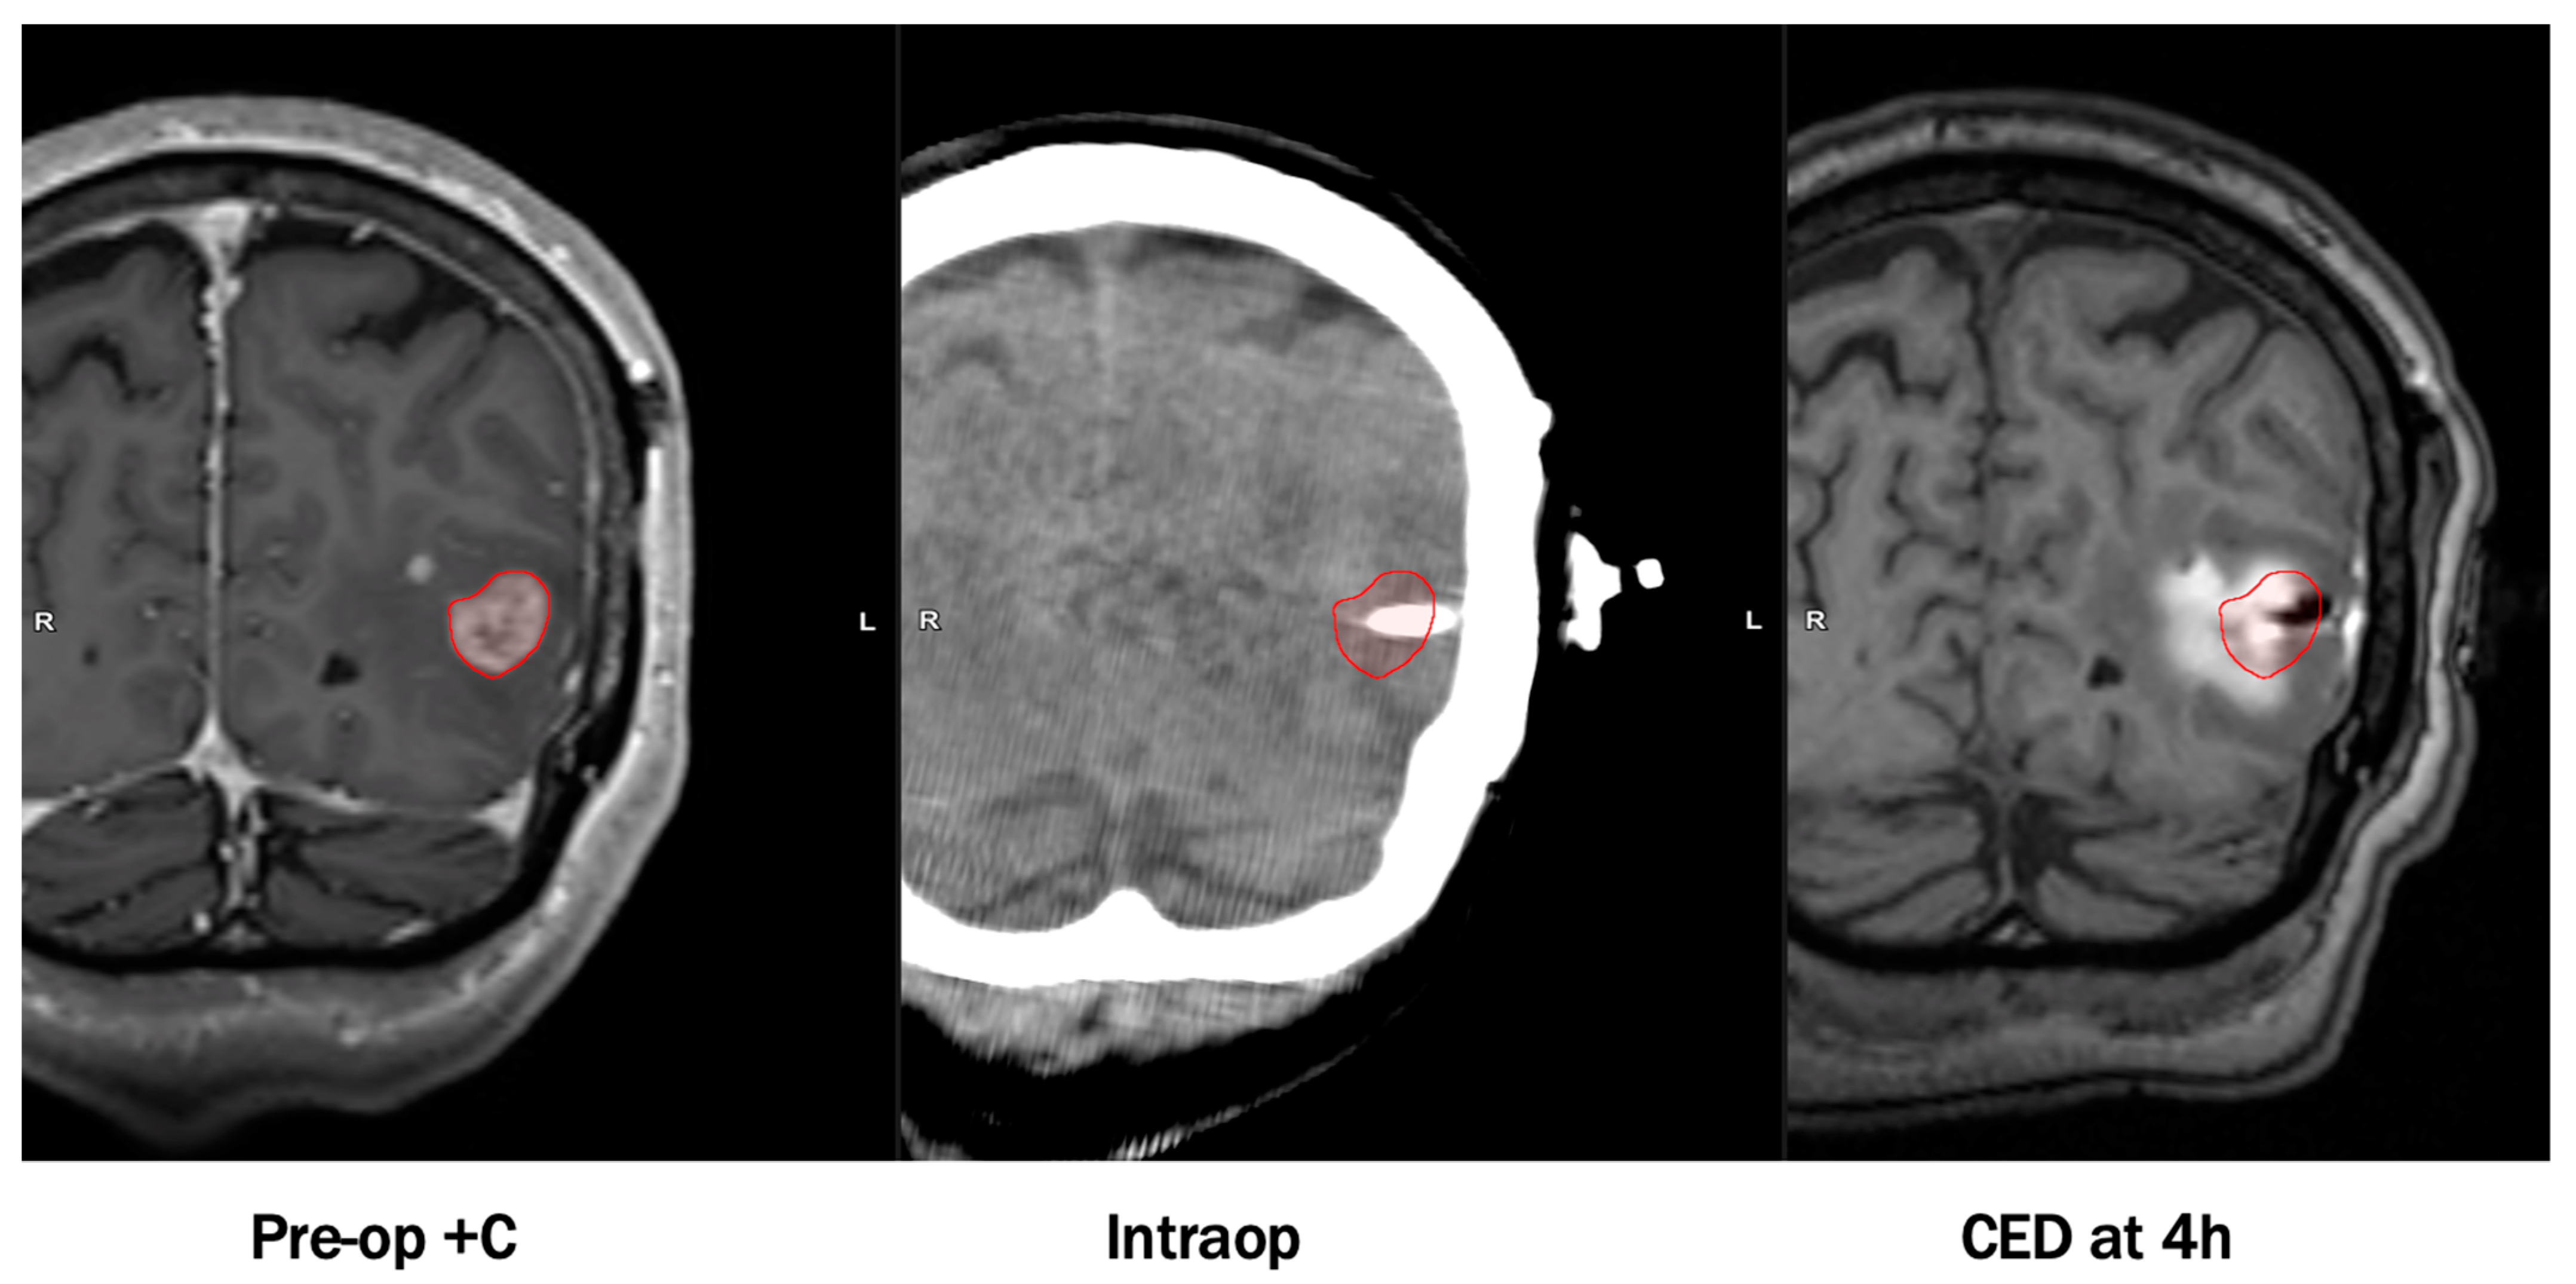

- Nwagwu, C.D.; Immidisetti, A.V.; Bukanowska, G.; Vogelbaum, M.A.; Carbonell, A.-M. Convection-Enhanced Delivery of a First-in-Class Anti-β1 Integrin Antibody for the Treatment of High-Grade Glioma Utilizing Real-Time Imaging. Pharmaceutics 2020, 13, 40. [Google Scholar] [CrossRef] [PubMed]